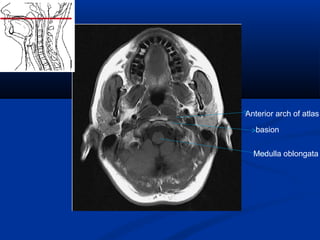

Medulla oblongata

basion

Anterior arch of atlas